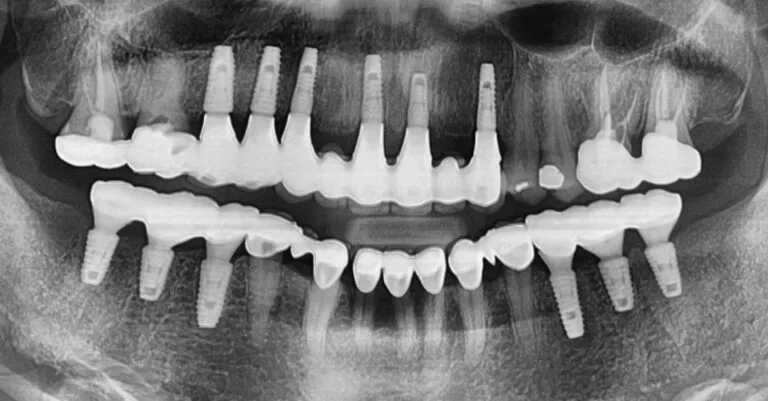

A 48-year-old gentleman sought relief at our Boston practice from persistent dental discomfort. Ten years prior, the loss of two upper left molars had understandably led him to favor his right side for chewing. This long-term compensatory habit resulted in significant strain and subsequent pain on his upper right side – a common scenario where […]